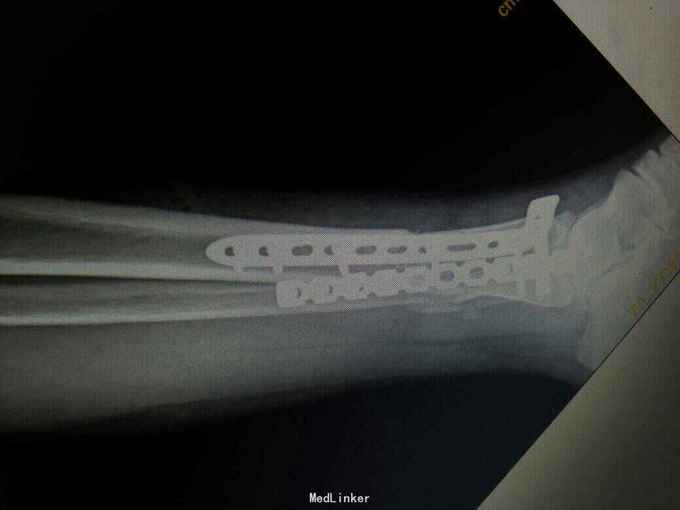

诊断:左胫腓骨下段开放性骨折。 治疗:考虑内侧有开放伤口,行内侧钢板固定感染概率大,我们采用前外侧入路,显露胫腓骨下段骨折端进行固定。

术后复查X线片提示骨折端对位对线好,伤口正常愈合,未出现感染。 讨论:患者内侧可见开放伤口,这时候采用内侧开放复位钢板固定感染概率大,我们采用前外侧切口,可避开内侧伤口,同时可清楚显露胫腓骨下段骨折端,并可有效固定。